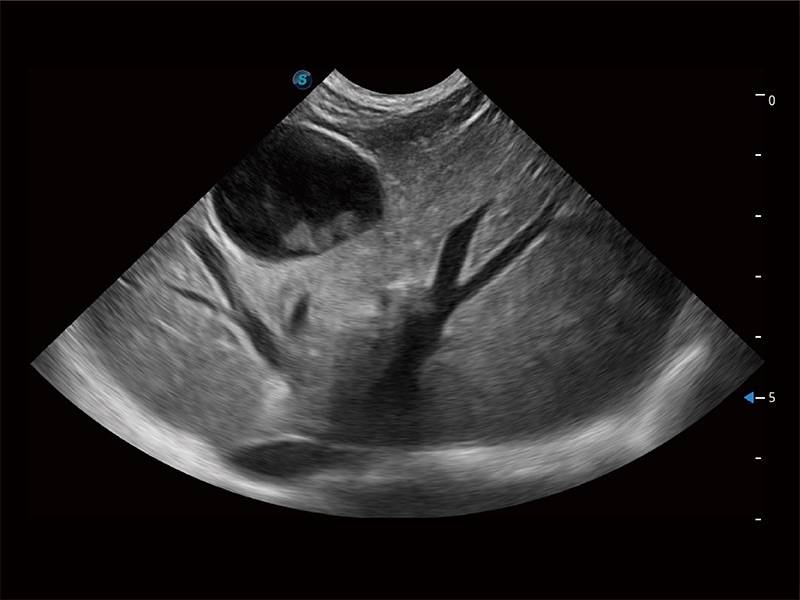

極大提升超低速微細(xì)血流的檢出能力,同時更精準(zhǔn)地濾除軟組織和超聲信號,為獸用醫(yī)生提供以往無法通過常規(guī)血流獲得的疾病診斷信息。